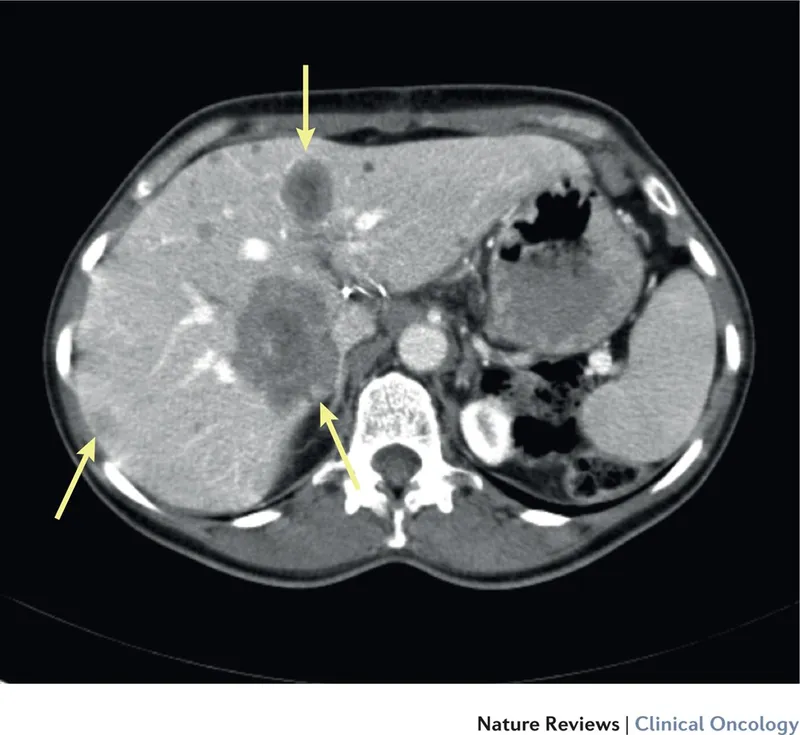

⭐ The most common sites for curative-intent metastasectomy are the liver (especially from colorectal cancer) and the lung. The goal is always an R0 resection (microscopically negative margins), as R1/R2 resections offer no survival benefit over non-operative management.

| Colorectal | Liver | ~50% |

- Liver: Post-hepatectomy liver failure (PHLF).

⭐ For liver metastasectomy, an adequate Future Liver Remnant (FLR) is critical. An FLR <20-25% (healthy liver) or <40% (damaged liver) risks fatal liver failure.